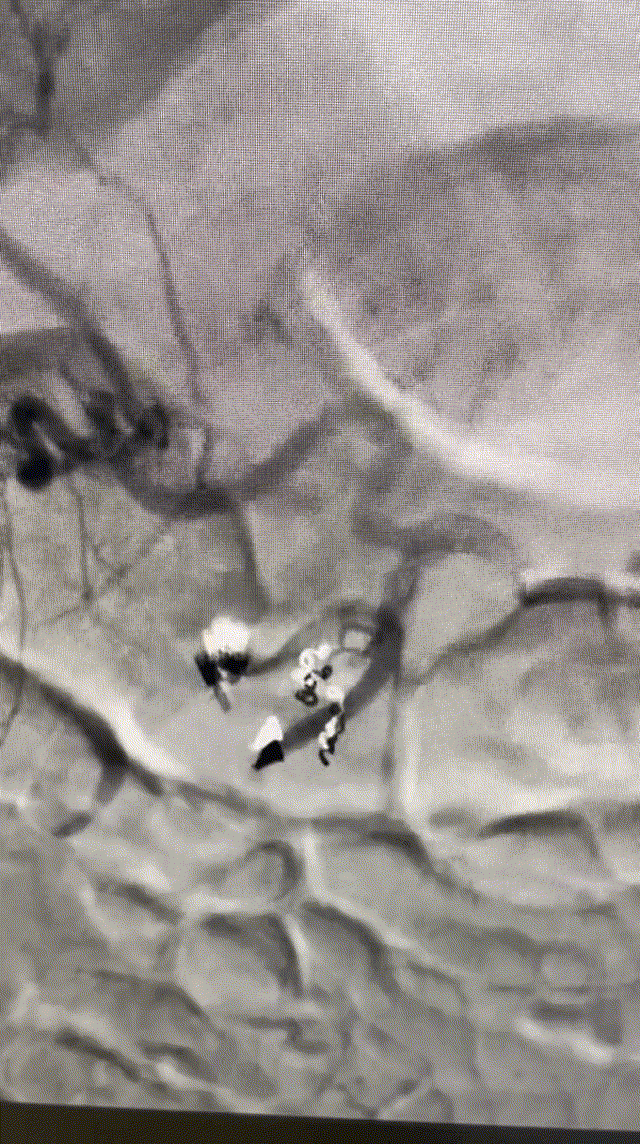

经过介入手术室积极准备,韩霜主任、余天垒主治医师为患者实施急诊胃十二指肠动脉栓塞术,术中造影可见十二指肠后上动脉造影剂外溢,遂使用微导丝微导管超选至十二指肠后上动脉及胃十二指肠动脉,使用弹簧圈及明胶海绵栓塞血管,造影满意后结束。手术过程顺利,病人安全返回病房。